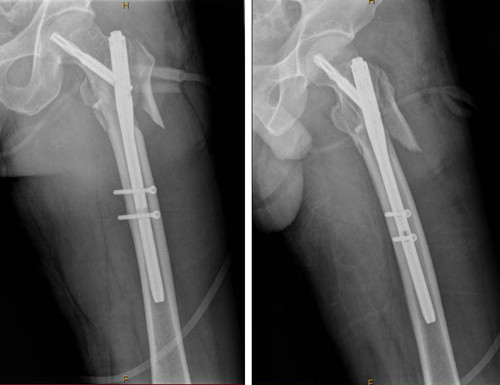

我院外一科成功開展PFNA(股骨近端髓內(nèi)釘)手術(shù)

原來,左股骨骨折的張先生在手術(shù)中接受了PFNA技術(shù)(股骨近端髓內(nèi)釘技術(shù)),張先生的手術(shù)所運用的新技術(shù)是樂從醫(yī)院去年12月成功開展來第三例了。

據(jù)了解,一個星期前,48歲的張先生在工作中不慎摔倒在地,左髖部受傷嚴(yán)重,入住外一科。經(jīng)X線查看,彭先生左股骨轉(zhuǎn)子下粉碎性骨折。針對彭先生的傷情,外一科骨科專家團(tuán)隊對治療方案進(jìn)行了慎密的思考和設(shè)定,外一科團(tuán)隊順利為張先生完成了“左股骨轉(zhuǎn)子下骨折切開復(fù)位PFNA內(nèi)固定術(shù)”。整個手術(shù)過程約1小時。術(shù)后第2天張先生已經(jīng)可以坐起,第5天已可坐在床邊活動左腿,第7天就能將左腿抬離床面,左腿功能也迅速得以恢復(fù)。

外一科主任蔡厚洪介紹說:PFNA技術(shù)是一種融合了微創(chuàng)技術(shù)的內(nèi)固定手術(shù)方式。該類手術(shù)由于其手術(shù)創(chuàng)傷小、手術(shù)時間短、術(shù)間出血少、術(shù)中術(shù)后并發(fā)癥發(fā)生率低、骨折愈合時間短力學(xué)穩(wěn)定性高等優(yōu)勢,病人能夠早期自主配合康復(fù)鍛煉,臨床療效非常滿意。

術(shù)后X線